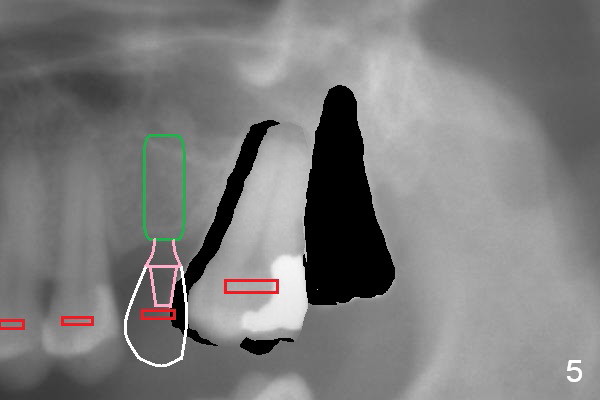

When the tooth #15 is distalized (Fig.3), place an implant at #14 (Fig.4 green), parallel to the tooth #13 and extract #16 (black). When the implant osteointegrates, place an abutment (Fig.5 pink), provisional (white) and bracket at #14. The implant is used as an anchorage to further distalize #15 until the latter reaches the normal position (Fig.6). CT study shows how much the tooth movement is needed prior to implantation.